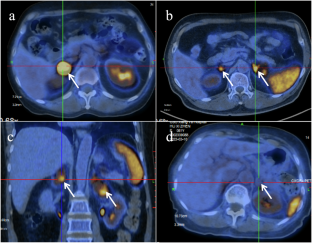

ACTH-independent Cushing syndrome (CS), a form of endogenous CS and an adrenal cause of hypertension, presents specific challenges in localizing cortisol-producing lesions. This study compared the diagnostic utility of 68Ga-Pentixafor PET/CT for lesion localization between ACTH-independent CS and non-functioning adrenal adenomas (NFAA). We retrospectively analyzed 73 subjects (52 with ACTH-independent CS; 21 with NFAA) undergoing 68Ga-Pentixafor PET/CT. Visual analysis demonstrated high diagnostic accuracy, with a sensitivity of 91.95%, a specificity of 95.24%, and a Youden index of 0.87. In semi-quantitative analysis, the lesion-to-adrenal ratio (LAR) showed superior performance compared to SUVmax and lesion-to-liver ratio (LLR). Using a diagnostic cutoff of SUVmax > 1.30, the sensitivity and specificity were 100% and 76.20%, respectively, supported by an AUC of 0.935 (P < 0.001) and a Youden index of 0.762. 68Ga-Pentixafor PET/CT effectively localizes functional adrenal lesions in ACTH-independent CS with high accuracy, supporting its role in guiding targeted management and surgical planning.

Ding J, Tong A, Zhang Y, Wen J, Zhang H, Hacker M, et al. Functional characterization of adrenocortical masses in nononcologic patients using 68Ga-Pentixafor. J Nucl Med. 2022;63:368–75.

Ding J, Tong A, Hacker M, Feng M, Huo L, Li X. Usefulness of 68Ga-Pentixafor PET/CT on diagnosis and management of cushing syndrome. Clin Nucl Med. 2022;47:669–76.